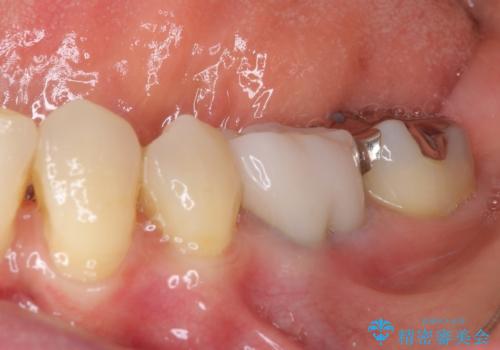

上唇小帯を切除したことで、ブリッジのダミー部分に触れて腫れていた歯肉は健全な状態になりました。

隙間もなくなったことで話す際の空気の漏れや、ものが挟まることもなくなりました。